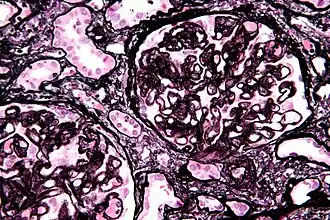

![]() Micrografía de una muestra de biopsia que revela nefropatía membranosa con proyecciones membranoides (spikes) prominentes de la membrana basal glomerular (tinción de Jones).[1] | ||

Entonces, la glomerulonefritis membranosa es una enfermedad caracterizada por depósitos inmunes subepiteliales y la formación de proyecciones membranoides ("spikes") perpendiculares de material similar a la membrana basal glomerular en la parte externa de dicha membrana (entre el citoplasma del podocito y la membrana). Como ya se dijo, puesto que en esta glomerulopatía en general no se detectan células inflamatorias y en algunos (o muchos) de los casos no hay una inflamación local prominente sino atrapamiento de complejos inmunes, algunos autores prefieren llamarla glomerulopatía membranosa o glomerulonefropatía membranosa; no obstante, el hecho de que haya inmunoglobulinas, complemento y complejo de ataque de membrana (C5b-9) presentes indica un proceso inflamatorio.[6] El curso clínico suele ser de progresión lenta hacia la cronicidad, con remisión espontánea y tendencia a las recaídas. Su incidencia es mucho mayor en los adultos que en los niños.[24] Los complejos inmunes activan una respuesta de las proteínas del sistema del complemento C5b a C9, que como se acaba de decir forman un complejo de ataque de membrana (CAM) sobre las células epiteliales del glomérulo. Este complejo de ataque, a su vez, estimula la liberación de proteasas y oxidantes provenientes de células mesangiales y epiteliales que dañan las paredes capilares y deteminan que se vuelvan porosas. Además, las células epiteliales parecen secretar un mediador desconocido que reduce la síntesis y la distribución de nefrina (componente proteico esencial de la barrera de filtración glomerular).[25]

Como ya se mencionó, la nefropatía membranosa es una causa frecuente de síndrome nefrótico del adulto,[26] trastorno poco habitual en los niños. También se mencionó que hay dos formas, primaria o idiopática (de causa desconocida) y secundaria o asociada con diversas enfermedades. A nivel óptico la lesión se caracteriza por el engrosamiento difuso de las membranas basales de los capilares glomerulares, lo que a nivel ultraestructural se relaciona con la presencia de depósitos electrodensos en el lado epitelial de la membrana basal, es decir entre dicha membrana y los podocitos. Esos depósitos, que en general se denominan depósitos subepiteliales o transmembranosos, determinan una progresión del proceso que se puede dividir en cuatro estadios según el sistema de Ehrenreich y Churg.[27]

En el estadio I la membrana basal es de grosor normal y no hay o solo hay mínimas proyecciones membranoides en el lado epitelial. Los depósitos subepiteliales son pequeños y la lámina densa en general no muestra alteraciones; las alteraciones del citoplasma de los podocitos son poco importantes. En el estadio II la membrana basal está engrosada y presenta formaciones espiculares similares a púas o dientes de peine en el lado epitelial; los depósitos electrodensos se ven entre las proyecciones membranoides. Esta alteración de la membrana basal es muy característica, se distingue claramente con las técnicas argénticas por el carácter argirófilo de la membrana y su presencia permite establecer el diagnóstico, si bien hay procesos que pueden simular una falsa imagen espicular de la membrana basal, por ejemplo en la amiloidosis, por la extensión de la sustancia amiloide hacia el lado epitelial. En el estadio III la membrana basal engrosada incorpora los depósitos electrodensos, que se hallan rodeados por las proyecciones membranoides. Por último, en el estadio IV la membrana basal presenta un engrosamiento irregular y un aspecto agujereado que le confieren los depósitos electrodensos de densidad variable, una lesión visible con la tinción tricrómica de Masson en microscopia óptica.[28] Se observa un engrosamiento global y difuso de la pared de los capilares glomerulares, a veces no evidente en las fases iniciales, que comienza por la formación de agregados inmunes subepiteliales. Con tinción argéntica se visualizan paredes capilares con imagen especular. En las fases avanzadas puede haber una esclerosis glomerular de grado variable. La celularidad del glomérulo suele ser normal. Por inmunofluorescencia se ven depósitos granulares difusos de IgG y C3. [29]